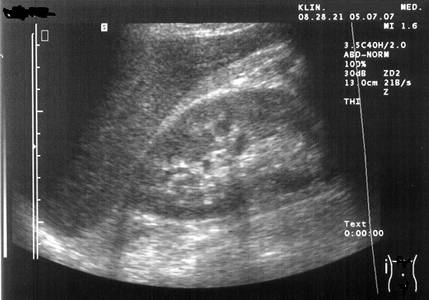

L’ecografia è una tipologia di indagine che consente di effettuare un esame diagnostico non invasivo. Più precisamente, la diagnostica ecografica è una metodica per immagini che utilizza onde sonore (ultrasuoni): con questa metodologia si riproducono, attraverso delle apparecchiature a ultrasuoni, delle mappe (ecografie) di parti del corpo, per verificare se sussistono eventuali malformazioni, tumori e patologie in generale.

Per eseguire l’esame ecografico si utilizza un apparecchio che si chiama ecografo o ecotomografo; il macchinario è dotato di una sonda (trasduttore): la sonda emette fasci di ultrasuoni che, attraversando i vari tessuti del corpo umano, generano fasci riflessi che ritornano al trasduttore (i cosiddetti echi di ritorno).

L’esame ecografico non è né doloroso, né fastidioso: il medico radiologo spalma un gel conduttore sulla pelle sopra il tratto da esplorare e muove su di essa la sonda che emette e riceve ultrasuoni. L’esame dura dai 10 ai 20 minuti, durante i quali il paziente deve evitare movimenti e deve, in certi momenti e su richiesta dell’esaminatore, trattenere il respiro.